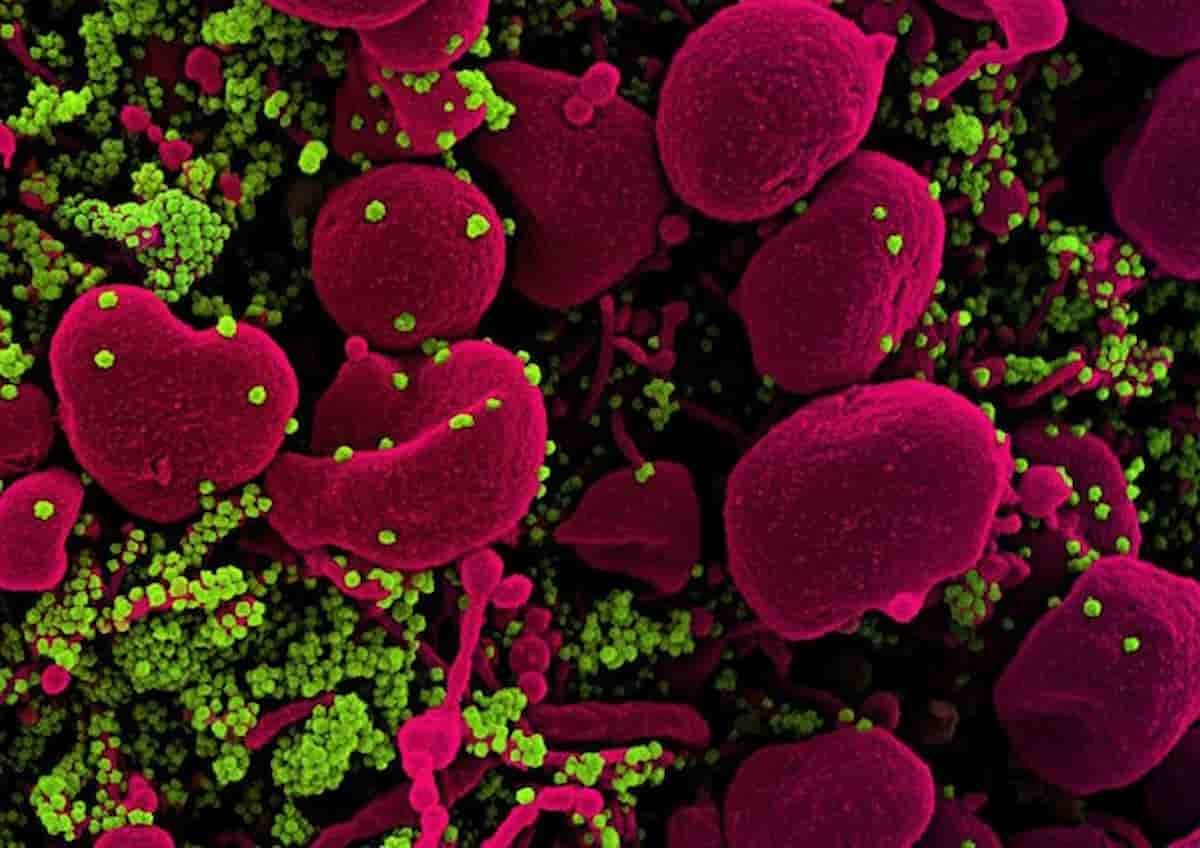

La Xec è la nuova variante del Covid che sta prendendo il sopravvento “spegnendo” le varianti rivali,...